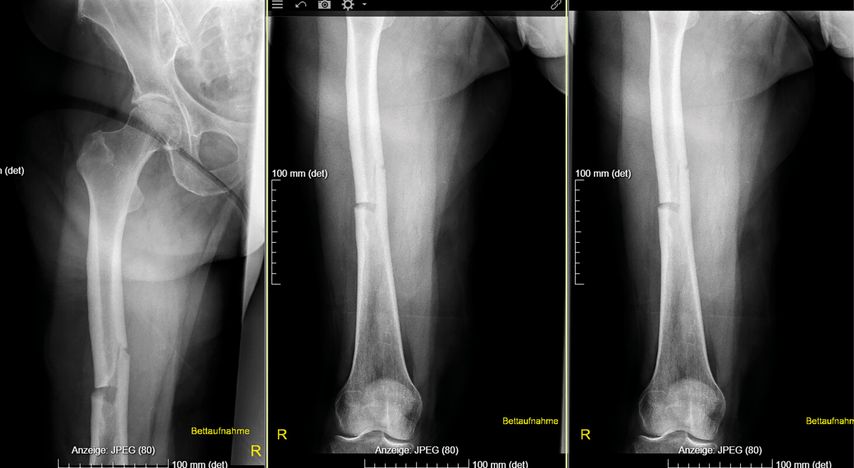

Eine Analyse der Femurfraktur in der Anamnese zeigte, dass es sich dabei um keine typische osteoporotische Fraktur am Femurhals, sondern um eine atypische Fraktur am Femurschaft unter Bisphosphonattherapie gehandelt hatte, wofür eine gerade Frakturlinie auf der lateralen und eine schräge Frakturlinie auf der medialen Seite sprachen (Abb.1).1 Der Fraktur waren keine Schmerzen vorausgegangen; diese gelten als Warnsignal für atypische Frakturen.2 Werden Patient:innen unter antiresorptiver Therapie mit unbestimmten Knochenschmerzen an den Oberschenkeln vorstellig, so sollte man hellhörig werden, erläuterte Rintelen.

Abb. 1: Die Röntgenaufnahmen zeigen eine atypische gerade Frakturlinie auf der lateralen und eine schräge Frakturlinie auf der medialen Seite